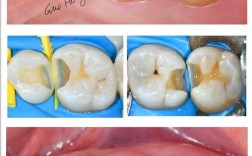

(图片来源网络,侵删)